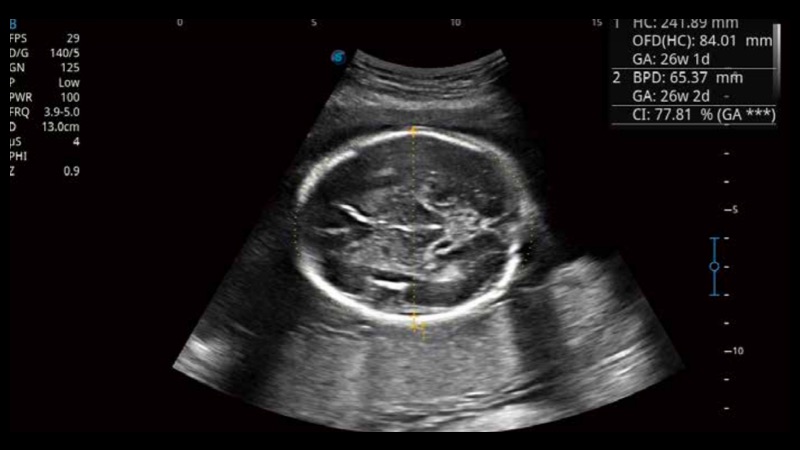

S-Fetus基于大數(shù)據(jù)深度學(xué)習(xí)算法,能夠幫助您在產(chǎn)前篩查過程中智能識別胎兒標(biāo)準(zhǔn)切面、自動測量并錄入報告。一個按鍵,即可智能、精準(zhǔn)、高效地獲取胎兒生理指標(biāo),極大簡化您的產(chǎn)科檢查操作。

可快速對產(chǎn)科掃查切面完成胎兒生理學(xué)參數(shù)的自動測量,減少操作者按鍵次數(shù),大幅提升檢查效率。

自動識別頸項透明層并獲得NT值,為早孕胎兒畸形篩查提供有效測量工具,提高診斷效率和診斷信心。